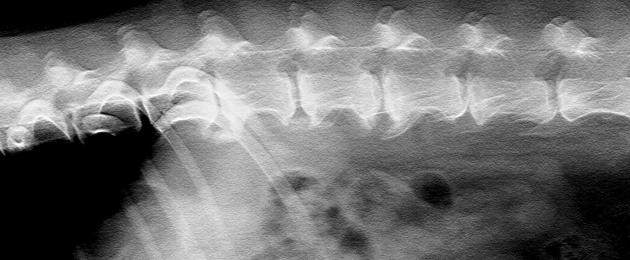

X-ray of the spine:

In case of locomotor difficulties, it is possible to identify vertebral lesions. on a radio without preparation. The injection of contrast product in the spine (myelography) is sometimes necessary to visualize possible compressions of the spinal cord (herniated discs) which can be responsible for paralysis in your animal.